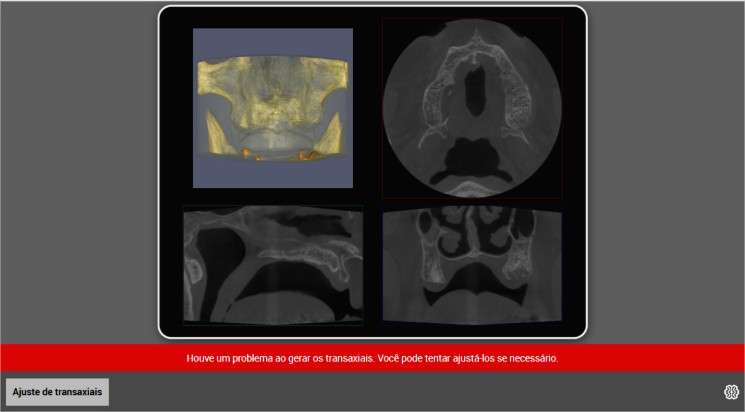

⚠️ Quando aparece o aviso “Problema ao gerar os transaxiais”

Esse aviso surge principalmente quando o paciente não possui dentes na região analisada, especialmente na maxila.

Como a IA usa os dentes como referência, a ausência deles dificulta a detecção automática.

✔ O que fazer?

-

Clicar no botão de ajuste

-

Marcar manualmente a região edêntula

-

Seguir a curvatura do osso alveolar

-

Recalcular cortes